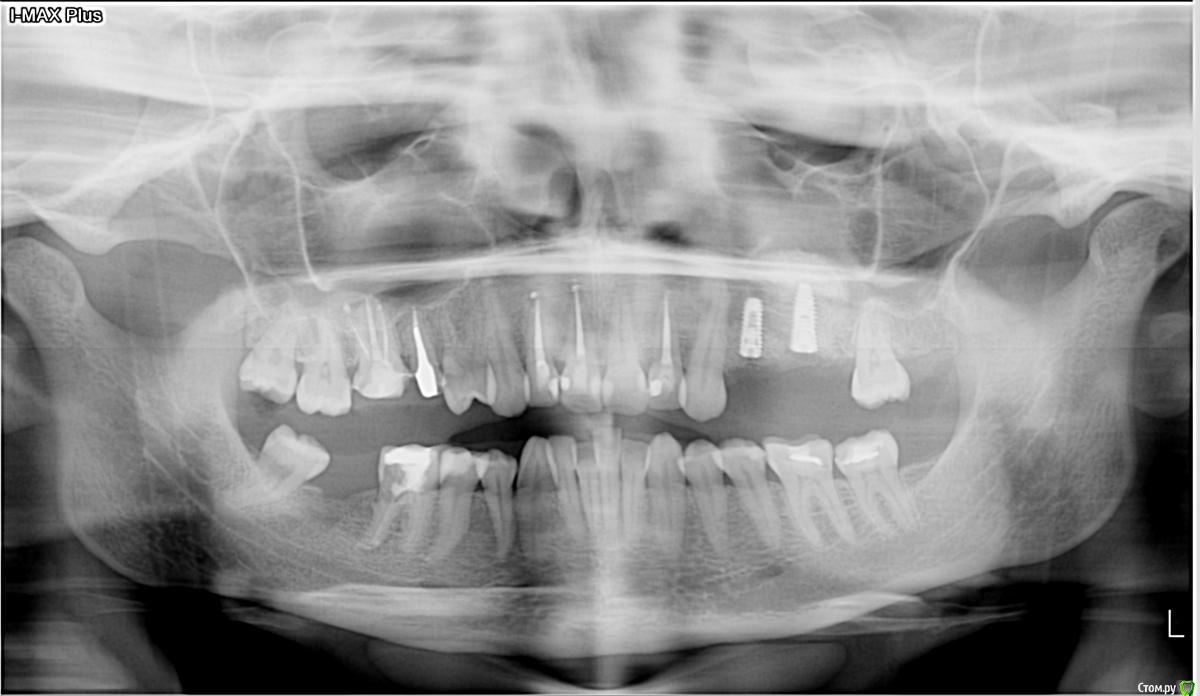

kamranchick Опубликовано 29 сентября, 2017 Поделиться Опубликовано 29 сентября, 2017 Господа, имеется проблема.Синус лифтинг с имплантацией произведено 7 сентябряНа этапе снятия швов все было хорошо.сегодня 29 сентября пациентка пришла с отеком, и говорит пару дней была температура... со стороны полости рта, гиперемия слизистой оболочки и боли в области проекции окнакакая тактика? Ссылка на комментарий